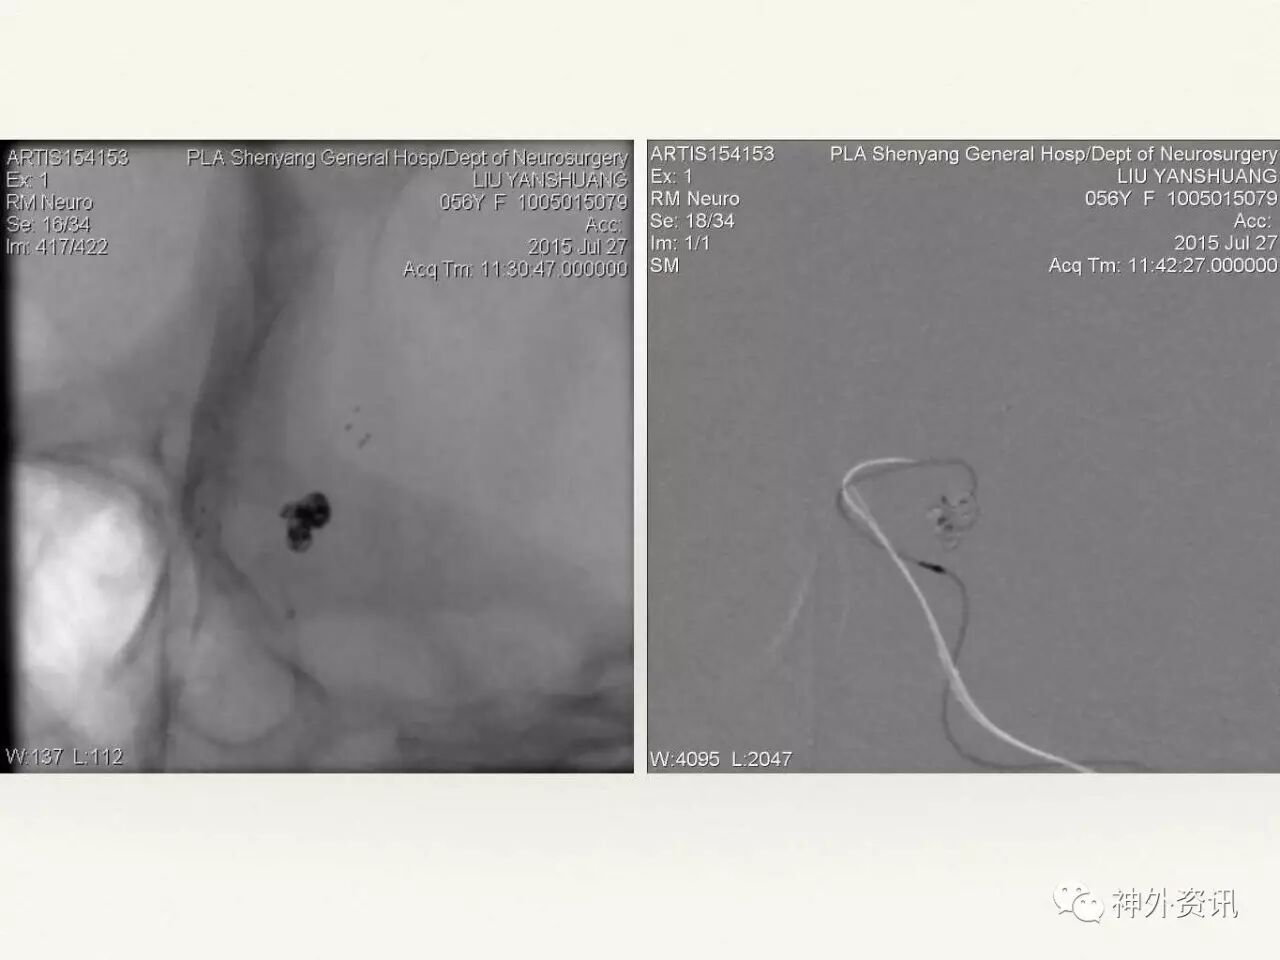

在东北地区率先开展了颈内动脉、大脑中动脉及基底动脉闭塞血管内再通、颅内动脉栓塞急性期取栓、血流导向装置治疗大型宽颈动脉瘤等,对颅内动脉瘤、动静脉畸形、颈动脉及颅内动脉狭窄、颈内动脉海绵窦瘘、硬脑膜动静脉瘘等外科治疗具有较深的造诣。完成脑血管造影8600余例,各类脑血管病介入手术共4500余例,动脉瘤、动静脉畸形、脑肿瘤、脑出血及脑外伤等外科手术1500余例。